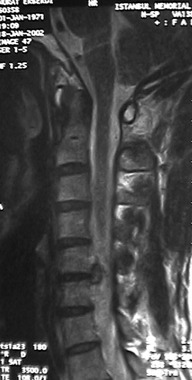

Boyunda ve kolda ağrı, ağrının ve duyu kaybının şekli, şiddeti, seyri ve eşlik eden diğer durumlar boyun fıtığı veya boyun omurgası kanal darlığını akla getirir. Ayrıntılı ve dikkatli bir nörolojik muayene bu kanaati güçlendirir. Günümüzde teşhisi kesinleştirmek için boyun omurgası MR incelemesi yapılır.

7. MR nedir?

Günümüzde boyun fıtığı ve diğer omurga hastalıklarının teşhisinde kullanılan başlıca tanı yöntemidir.MR, omurlar, disk yastıkçıkları, sinir kökleri ve omurilik hakkında ayrıntılı bilgi sağlamaktadır.